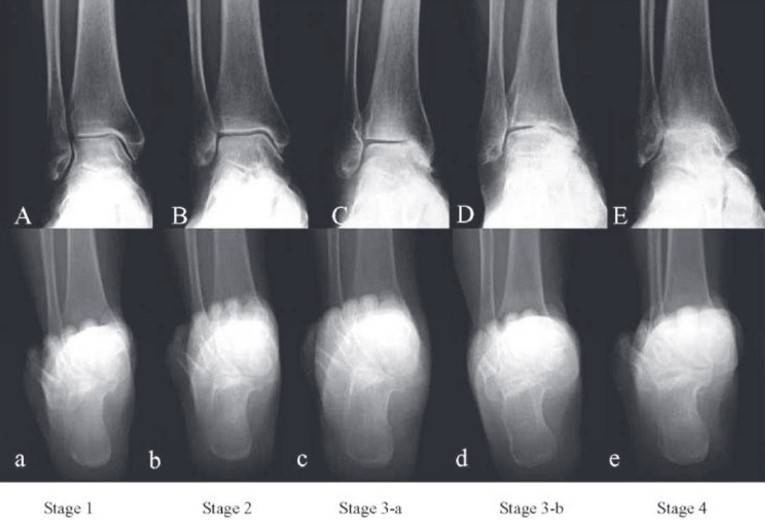

Treatment Options for Ankle Arthritis by Stage

1. Early Ankle Arthritis

2. Mid-Stage Ankle Arthritis

3. Late-Stage Ankle Arthritis

When degenerative ankle arthritis reaches an advanced stage, surgical intervention becomes essential, with the most common options being: